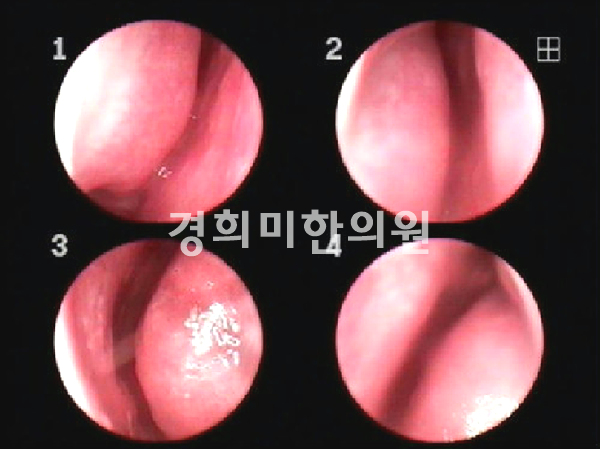

경희미의원 코내시경, 비내시경, 경상코점막의 발적을 관찰하여 2차 세균 감염이 일어나지 않을 경우 점액기로 옮김과 동시에 호전됩니다.통상적으로 증상이 사라지기까지 5~10일 소요됩니다.

경희미의원 진단, 치료를 먼저 10세 여아의 급성 비염 비내시경 치료 전후 사진을 소개합니다.

치료전(좌) → 치료후(우) 여 / 10세, 급성 비염, 2주 치료기간

비염은 정확한 진단이 우선입니다.급성 및 만성 비염, 축농증, 알레르기 비염의 경우 증상이 다를 뿐만 아니라, 코의 내시경 검사 코 점막과 콧물의 양상도 다릅니다.그리고 중이염 여부도 확인해 보도록 합시다.경희미의원은 조재훈 원장이 직접 코내시경을 통해 코 점막의 상태를 확인합니다.주요 치료는 면역 관련 한약이기 때문에 빈번하게 병원을 방문할 필요가 없습니다.